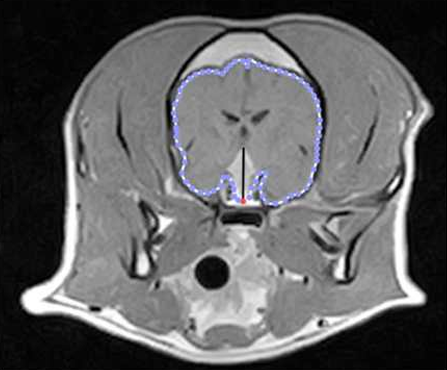

| MRI : ์ฟ ์ฑ๋ง ์๋ ํ์์์ ์ ์ฐ์ง X - ์ ์ข โ ๋ํ์์ฒด ๋น๋ (P:B ratio < 0.31) - ๋ํ์์ฒด ํฌ๊ธฐ๊ฐ 1cm ์ด์์ด๋ฉด ์ ๊ฒฝ์ฆ์ ๊ฐ๋ฅ | ![]() |